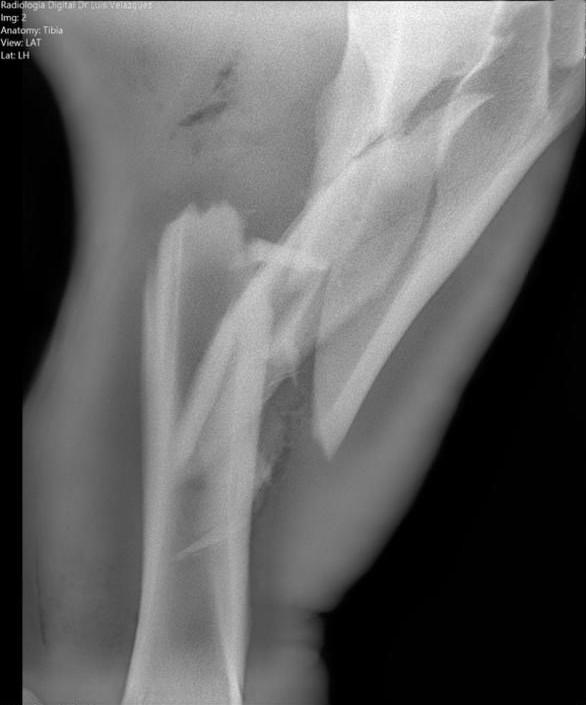

Cambios Térmicos en las Extremidades de Caballos,

Asociados a Golpes y su Evaluación por Termografía.

Los caballos de salto, en competencia, pueden derribar obstáculos y lastimarse. Si se golpean, no siempre claudican. Considerando al calor como un signo de inflamación, se evaluaron los cambios térmicos de 6 áreas de las extremidades torácicas y pelvianas de 23 caballos de salto en nivel de competencia de 1.05 a 1.60 m de altura, por medio de termografía durante 4 días de competencia (N=2208 áreas).